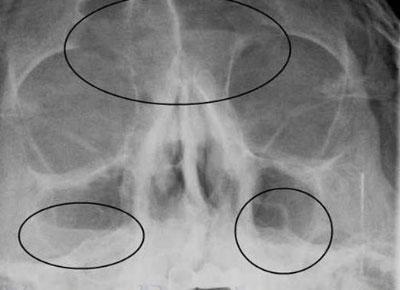

Если у врача есть подозрения на воспаление верхнечелюстных пазух, то пациенту назначают рентген или компьютерную томографию. Эти два метода обследования позволяют абсолютно точно увидеть признаки гайморита у детей.

Рентген не всегда может быть информативен в постановке диагноза у ребёнка. Слизистая оболочка носовой полости у детей довольно плотная и отекает при любых инфекционных процессах в носоглотке. На снимке отёкший участок просматривается как затемнение пазухи, что не всегда соответствует действительности.